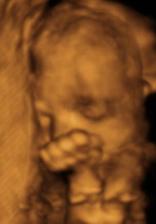

21.3. 4D ultrazvuk - neskutečně krááááásnýýýýýý.........za odměnu jsme pro mimi nakoupili skříně a další věci do pokojíčku